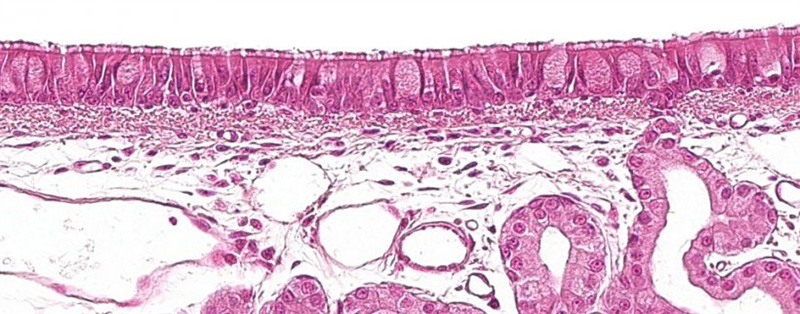

ºôÎüµÀºÍÏû»¯µÀÊÇ·ÇÖÞÖíÎÁ²¡¶¾ÈëÇÖµÄÖ÷ÒªÃÅ»§£¬µ¥ºË-¾ÞÊÉϸ°ûÊDz¡¶¾µÄÖ÷Òª°Ðϸ°û¡£²¡¶¾Ö÷Ҫͨ¹ý¾Þ°ûÒû»ò Íø¸ñµ°°×½éµ¼µÄÄÚÍÌÍê³ÉÆäÈëÇÖ¡£Ëæºó¾­ÑªÒººÍ»òÁܰÍ×ªÒÆÖÁÁܰͽá¡¢¹ÇË衢Ƣ¡¢¸ÎºÍÉö¶þ´Î¸´ÖÆ¡£

ÖíºôÎüµÀð¤Ä¤

ËùÓÐճĤÉÏÆ¤×éÖ¯£¨Ö÷ÒªÊÇÏû»¯µÀ/ºôÎüµÀ£©¹ÌÓвãÖж¼ÓоÞÊÉϸ°ûºÍ µ¥ºËϸ°û¡£µ±Õ³Ä¤ÉÏÆ¤×éÖ¯ÆÆËðʱ£¬¾ÞÊÉϸ°û»á´óÁ¿¾Û¼¯£¬Ó벡¶¾Ö±½Ó½Ó´¥¡£